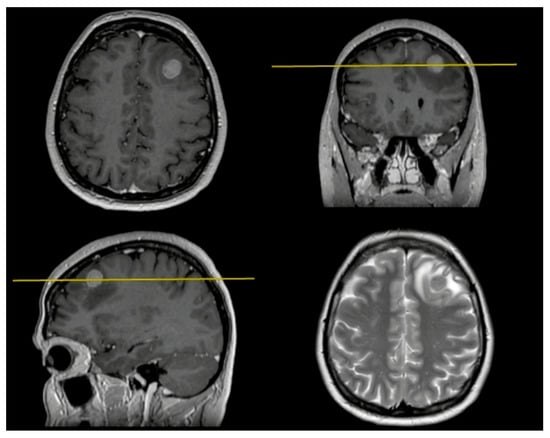

In this case example, we describe the en-bloc resection technique of BM. We present a 47 y.o. female patient with a previous history of breast cancer treated 1 year before. The neuroradiological findings showed a single metastasis located into the left frontal lobe (Figure 2). No more metastases were found after a total body CT scan.

Figure 2.

Preoperative MRI shows a BM located under the left middle frontal gyrus.